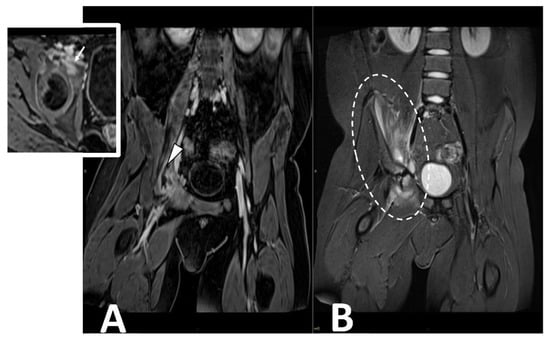

2.5. Infectious Myositis

- Bickels, J.; Ben-Sira, L.; Kessler, A.; Wientroub, S. Primary pyomyositis. J. Bone Joint. Surg. Am. 2002, 84, 2277–2286. [Google Scholar] [CrossRef]

- Thammaroj, P.; Panitchote, A.; Muktabhant, C.; Chowchuen, P. Discrimination between tuberculous and bacterial pyomyositis in magnetic resonance features. Eur. J. Radiol. Open 2020, 7, 100214. [Google Scholar] [CrossRef]

- Hernandez, R.J.; Strouse, P.J.; Craig, C.L.; Farley, F.A. Focal pyomyositis of the perisciatic muscles in children. AJR Am. J. Roentgenol. 2002, 179, 1267–1271. [Google Scholar] [CrossRef]

- Gonzalez Moran, G.; Garcia Duran, C.; Albiñana, J. Imaging on pelvic pyomyositis in children related to pathogenesis. J. Child. Orthop. 2009, 3, 479–484. [Google Scholar] [CrossRef]

- Schulze, M.; Kötter, I.; Ernemann, U.; Fenchel, M.; Tzaribatchev, N.; Claussen, C.D.; Horger, M. MRI findings in inflammatory muscle diseases and their noninflammatory mimics. AJR Am. J. Roentgenol. 2009, 192, 1708–1716. [Google Scholar] [CrossRef] [PubMed]